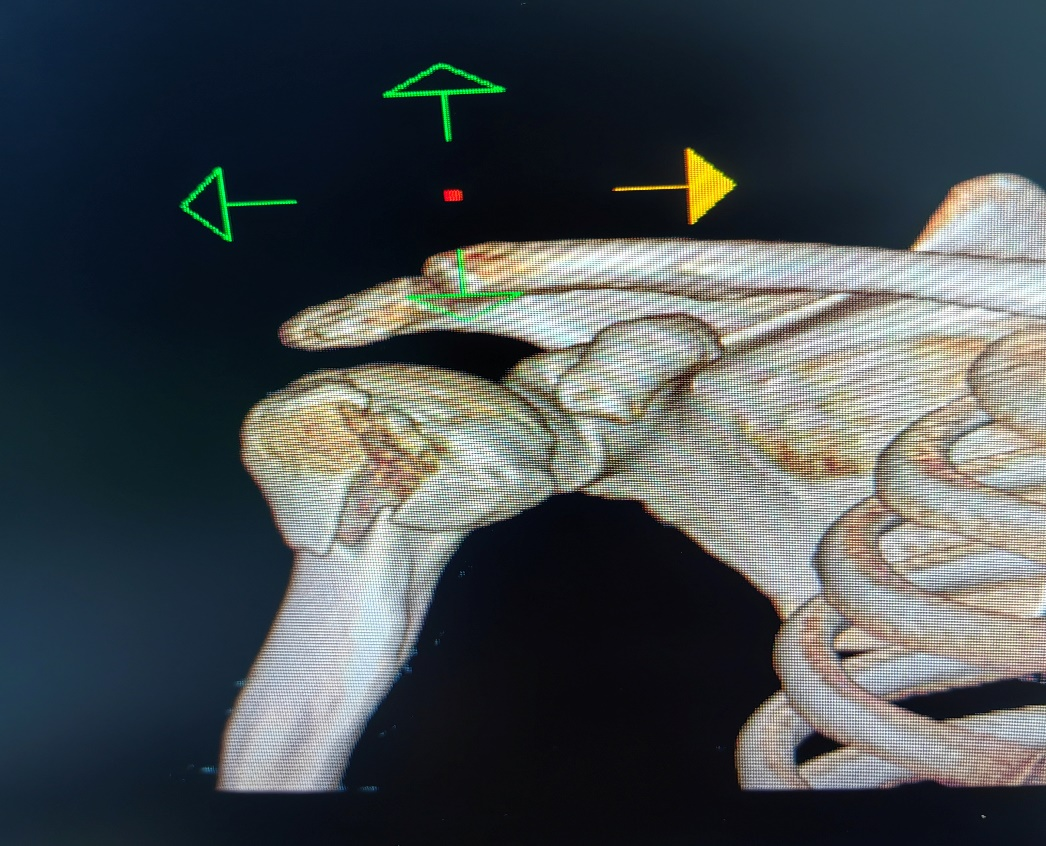

近日,我院骨科成功开展肩关节镜下大结节骨折内固定+肩袖修补术。患者,男,46岁,因右肩摔伤肿痛活动受限入院。CT示:右肱骨大结节骨折。MR检查提示:右冈上肌腱损伤。完善术前准备后,行“肩关节镜下右肱骨大结节骨折内固定术+肩袖修补术”,手术非常顺利,术后我院康复团队介入早期康复,加快了患肩功能锻炼的进程,患肩功能恢复良好。

肱骨大结节骨折是肱骨近端骨折中常见的骨折类型之一,肱骨大结节骨折后肩袖肌腱的力臂遭到破坏,特别是在肩关节外展时,严重影响了肩关节功能。移位的大结节减低了肩峰下间隙,导致肩关节在外展活动时出现撞击,使肩关节的功能和活动范围受到影响。因此,治疗移位明显的肱骨大结节骨折不但需要坚强固定,同时需要解剖复位。随着肩关节镜的发展,关节镜下治疗大结节骨折已被越来越广泛的应用。关节镜下可采用空心钉、克氏针、双排锚钉(双线桥)等方式进行固定,根据不同骨折类型可以多种术式相互结合使用。对肱骨大结节骨折块较小、粉碎严重的骨折难以达到解剖复位,坚强固定,术后容易出现内固定失效,因此对于肱骨大结节粉碎性骨折,建议采用双排锚钉缝线桥技术固定大结节骨折,内、外排带线锚钉的尾线交织成“网状”线桥,将粉碎的大结节骨折块完全覆盖在骨折的足印区,达到精确复位,坚强固定。缝线桥技术的适应证为单纯的肱骨大结节骨折,骨折粉碎性,骨折范围直径<3 cm。对于较大骨折块,可以选用带线锚钉缝线桥技术固定肱骨大结节骨折时,结合空心钉固定。肩关节镜下双排锚钉缝线桥技术治疗肱骨大结节撕脱骨折,对肩关节外科医生技术要求较高,具有一定学习曲线。肩关节镜下不仅能有效固定大结节骨折,还可修复合并损伤如Bankart损伤、肱二头肌长头肌腱损伤、SLAP损伤,效果令人满意,目前是一种有效的肱骨大结节撕脱骨折的微创治疗方案。